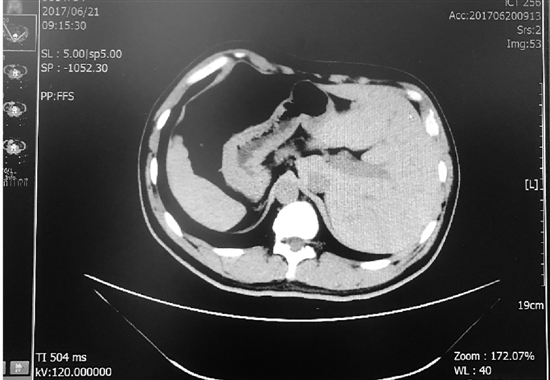

张先生的肝脏在左侧,脾脏在右侧,与正常人相反。